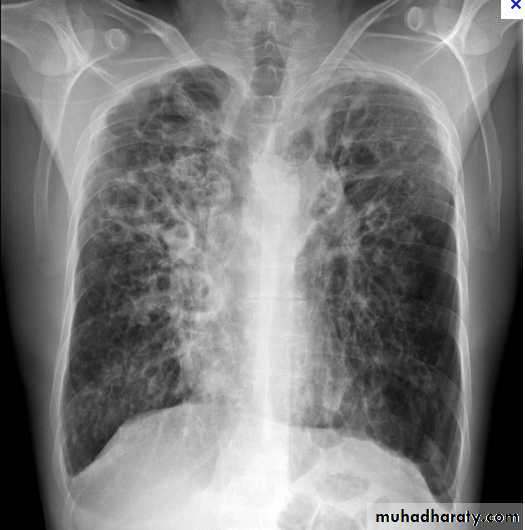

Miliary Tuberculosis. A cone-down view of a frontal radiograph demonstrates innumerable micronodular opacities characteristic of micronodular (miliary)

interstitial disease.

Transbronchial biopsy demonstrated caseating granulomas containing acid-fast bacilli.

Miliary TB

a frontal radiograph demonstrates innumerable micronodular opacities characteristic of micronodular (miliary) interstitial disease. Transbronchial biopsy demonstrated caseating granulomas containing acid-fast bacilli.Tuberculoma